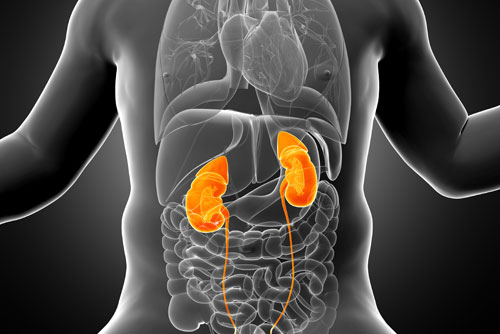

1 -  Böbrek Anomalileri Fetal Anomali Taraması

Bebekte oluşan böbrek anormallikleri yapılacak fetal anomali taraması ile belirlenebiliyor. Bebekte küçük böbrekten, yerinde olmayan böbreğe ya da böbrek yokluğuna kadar pek çok oluşabilecek sorun tespit edilebiliyor. Bebeklerde sık rastlanan böbrek anormalliklerinin hayati tehlike taşımadığı belirtilirken, bazı anormalliklerin ise, ileri yıllarda böbrek hastalıklarına neden olabileceği belirtiliyor. Günümüzde birçok böbrek anomalisi tedavi edilebiliyor.